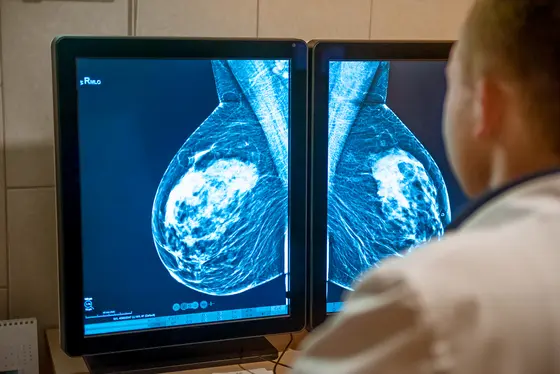

Breast cancer is as manifold as are those who are affected. Therefore, scientists and physicians from the German Cancer Research Center (DKFZ), Heidelberg University Hospital (UKHD) and the National Center for Tumor Diseases (NCT) in Heidelberg are generating genetic profiles from metastatic tissue samples before they choose, on this basis, an appropriate therapy tailored to the individual patient. In this way, they endeavor to improve curative chances and lower the risk of side effects.

In a first step, Lichter and his team analyze tissue samples of metastases from patients with advanced breast cancer. In this way, the scientists first generate a genetic profile of each study participant. “In this way, we can identify individual differences in breast cancer cases much more precisely than it has been possible up to now,“ says molecular geneticist Lichter.